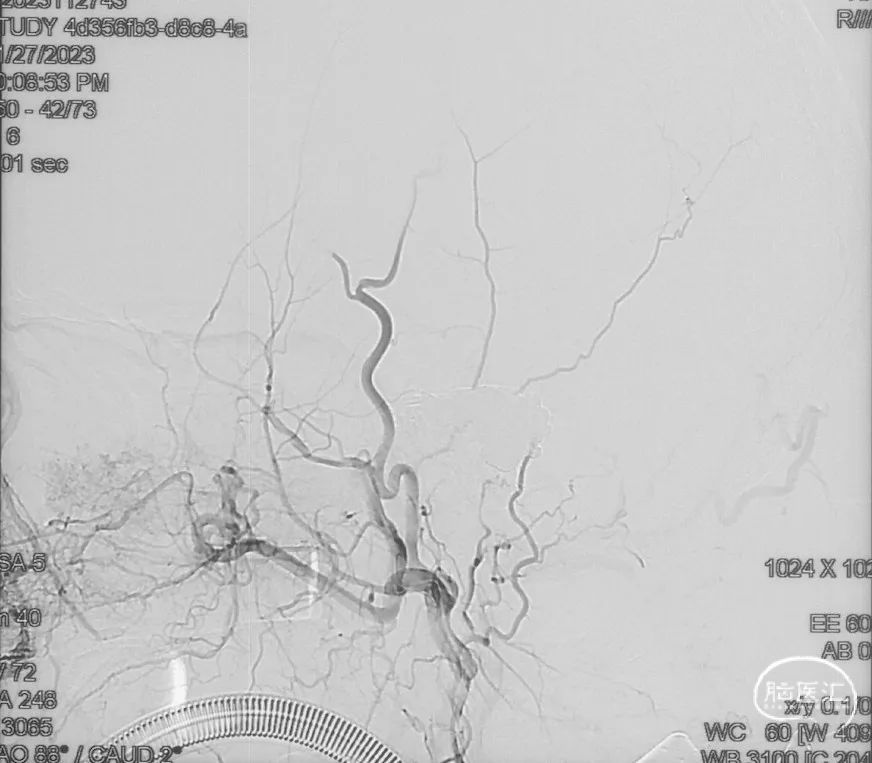

治疗结果

双侧颈外、颈内动脉正侧位造影瘘口均不显影

双侧椎动脉造影未见瘘口显影,可见广泛皮层静脉瘀滞

Onyx胶铸型显示瘘口形态。